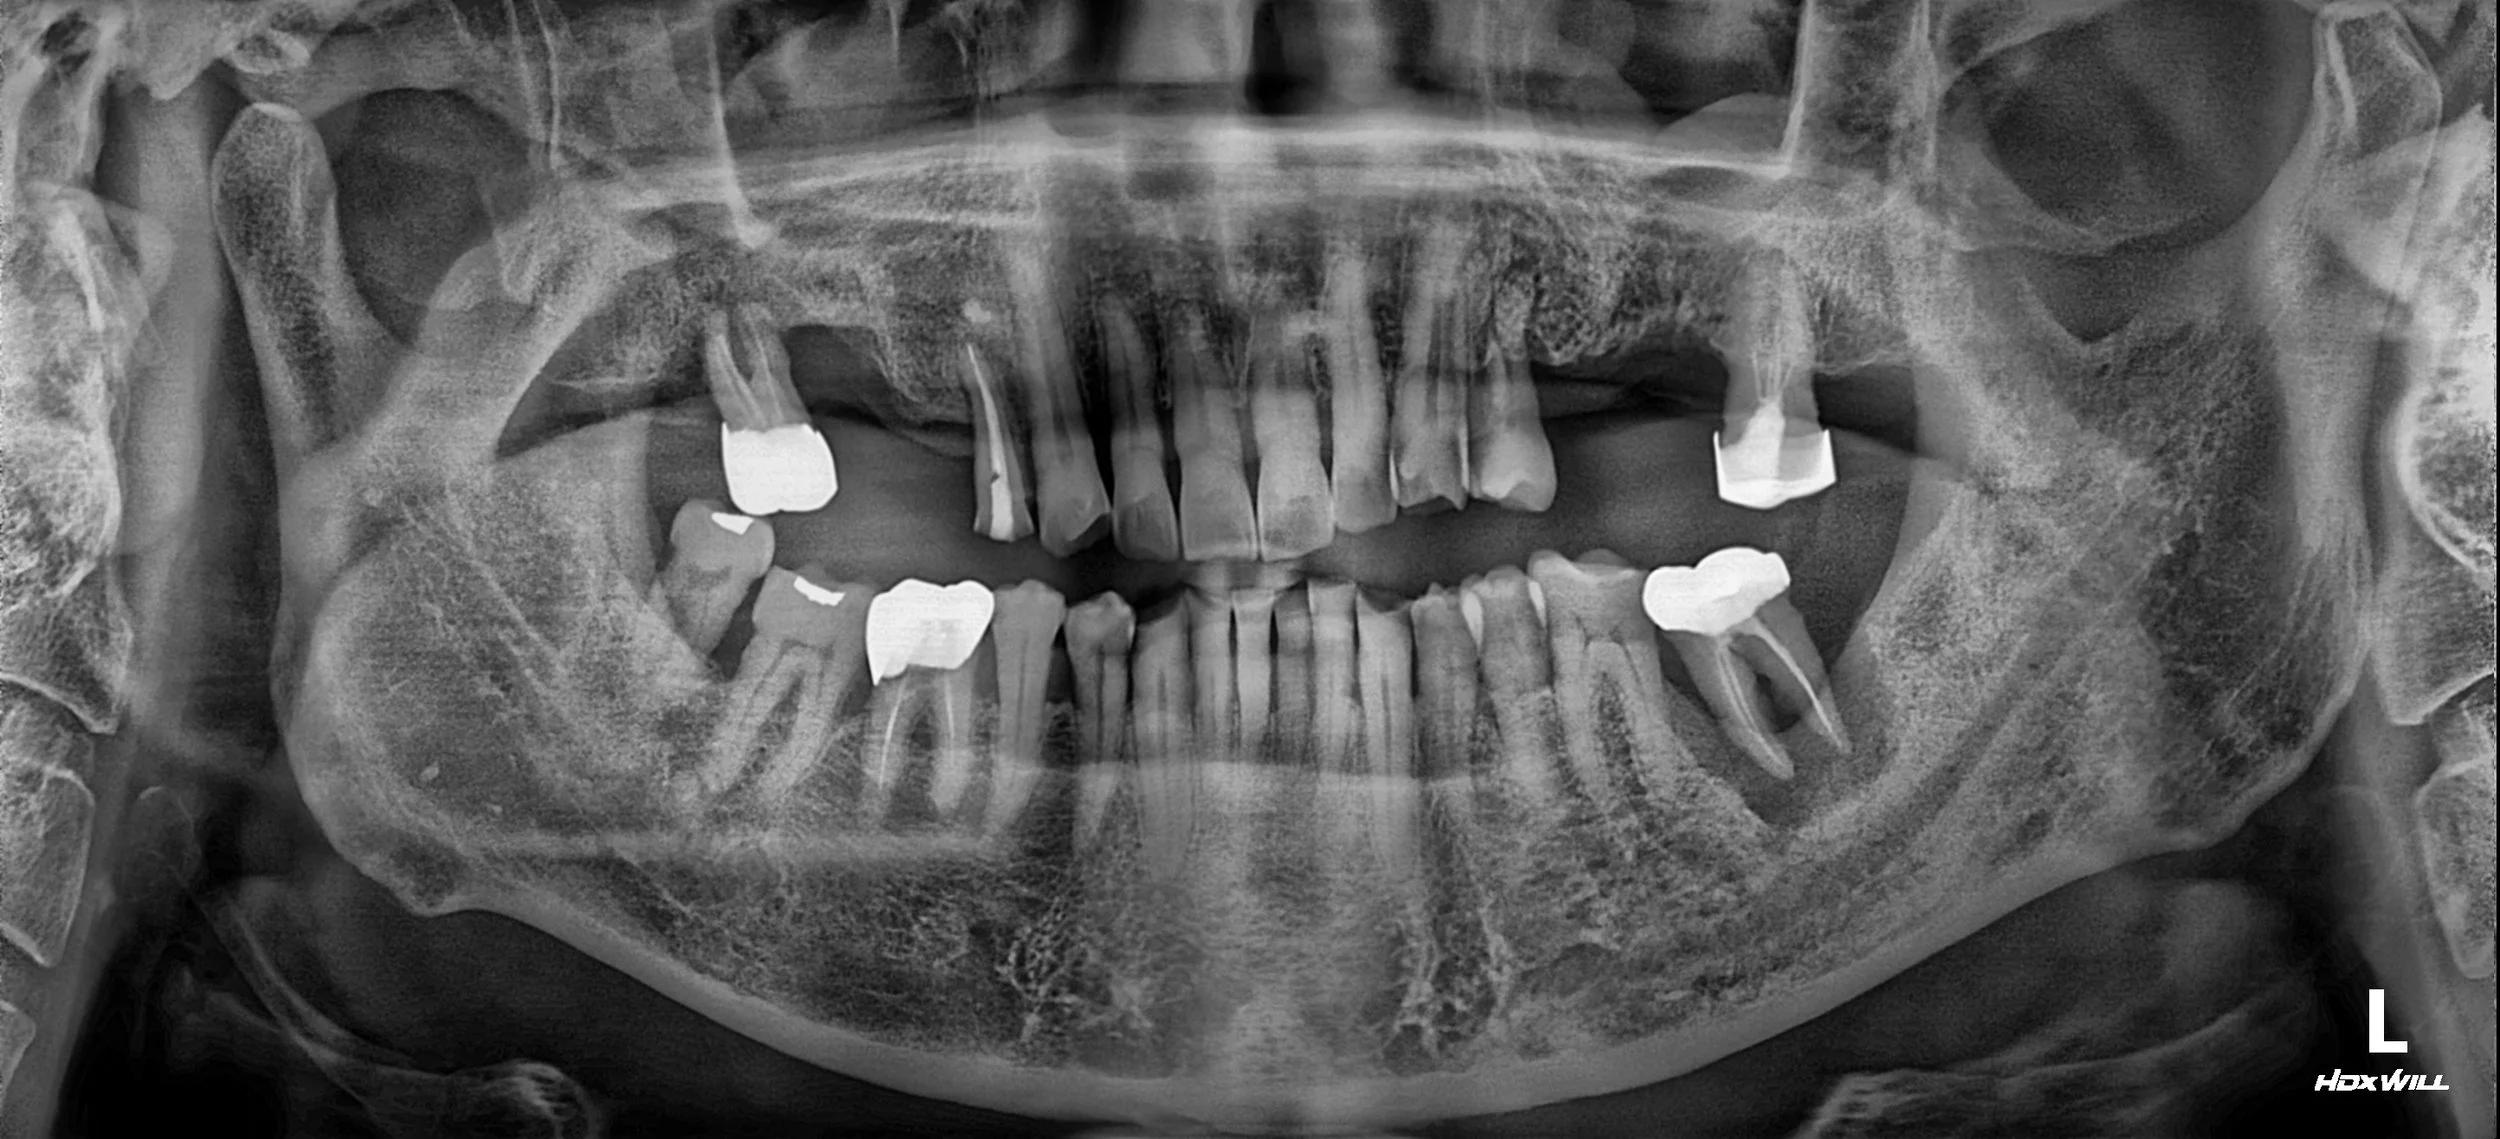

35. Comprehensive Full-Arch Transformation: Restoring Confidence in a Young Phobic Patient

Reversing the effects of generalized rampant caries and occlusal collapse in a female patient in her 20s. A tooth-preserving, implant-assisted approach focused on stable VDO elevation and overcoming social anxiety.